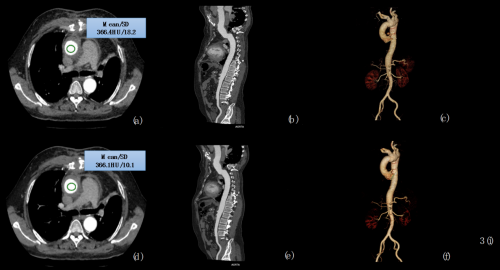

在主動脈“雙低”掃描的情況下,基于人工智能的圖像優(yōu)化能夠有效降低噪聲、提高 SNR 和CNR ,明顯改善主動脈 CTA 的整體圖像質(zhì)量;與常規(guī)掃描輻射劑量與對比劑用量相比,輻射劑量降低約 79.18% ,對比劑用量降低約 50%。

▲通過 AI 優(yōu)化,“雙低”掃描的圖像質(zhì)量得到顯著提升

這意味著NeuViz 128 精睿 CT的AI成像優(yōu)化技術(shù),不僅可幫助醫(yī)生實現(xiàn)圖像降噪,提高診斷效果,減少漏診和誤診;還可為患者檢查,尤其是嬰幼兒檢查提供了更低劑量的檢查方案,更加安全。